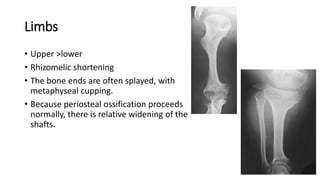

Limbs

• Upper >lower

• Rhizomelic shortening

• The bone ends are often splayed, with

metaphyseal cupping.

• Because periosteal ossification proceeds

normally, there is relative widening of the

shafts.